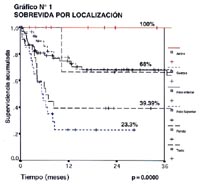

En el Gráfico N° 1, se puede apreciar la relación de la supervivencia acumulada y el tiempo en meses respecto a la localización de la neoplasia en el estómago y lo primero que sobresale es el hecho de que los pacientes con Linfoma en antro tienen una mejor sobrevida respecto a aquellos pacientes cuya localización está referida al polo superior gástrico (área cardial, fondo y cuerpo proximal), lo que se muestra en el gráfico con curvas en ambos extremos, también se ve que la localización en todo el estómago tiene una baja supervivencia, bastante cercana y paralela al polo superior; de otro lado, la localización de la lesión en el cuerpo y en el polo inferior (cuerpo + antro), tienen ambas una supervivencia a 3 años semejante y por encima del 60%, expresando todas estas curvas una clara significancia estadística de p=0.0000.

Para contrastar la realidad de manejo de nuestros pacientes con Maltoma que ya se ha referido, existen reportes donde se hace el manejo del Maltoma utilizando la ecoendoscopía (34), y seleccionando sobretodo a aquellos pacientes con estadio clínico I-II que tienen el compromiso sólo de la mucosa y/o submucosa encontrándose una remisión completa de la enfermedad hasta del 79% de los casos siempre que no exista compromiso ganglionar (80). Más aún, hay series que revelan como factores altamente favorables para la remisión completa de la enfermedad del Maltoma con antibióticoterapia, cuando la lesión superficial está circunscrita a la mucosa o submucosa, ausencia de compromiso ganglionar y localización distal (90). Nosotros hemos encontrado tanto en el análisis univariado como en el análisis multivariado que la localización distal o antral de nuestros 169 pacientes, se correlaciona con un excelente pronóstico llegando a una supervivencia acumulada a 36 meses del 100%, respecto a una supervivencia que alcanza el 23% a 3 años cuando la localización del Linfoma es proximal (p=0.0000), nuestros datos concuerdan con otras series que encuentran que la localización distal tiene una remisión completa del 100% respecto a la localización proximal que sólo alcanza el 27% y con una significancia estadística de p=0.006 (90).